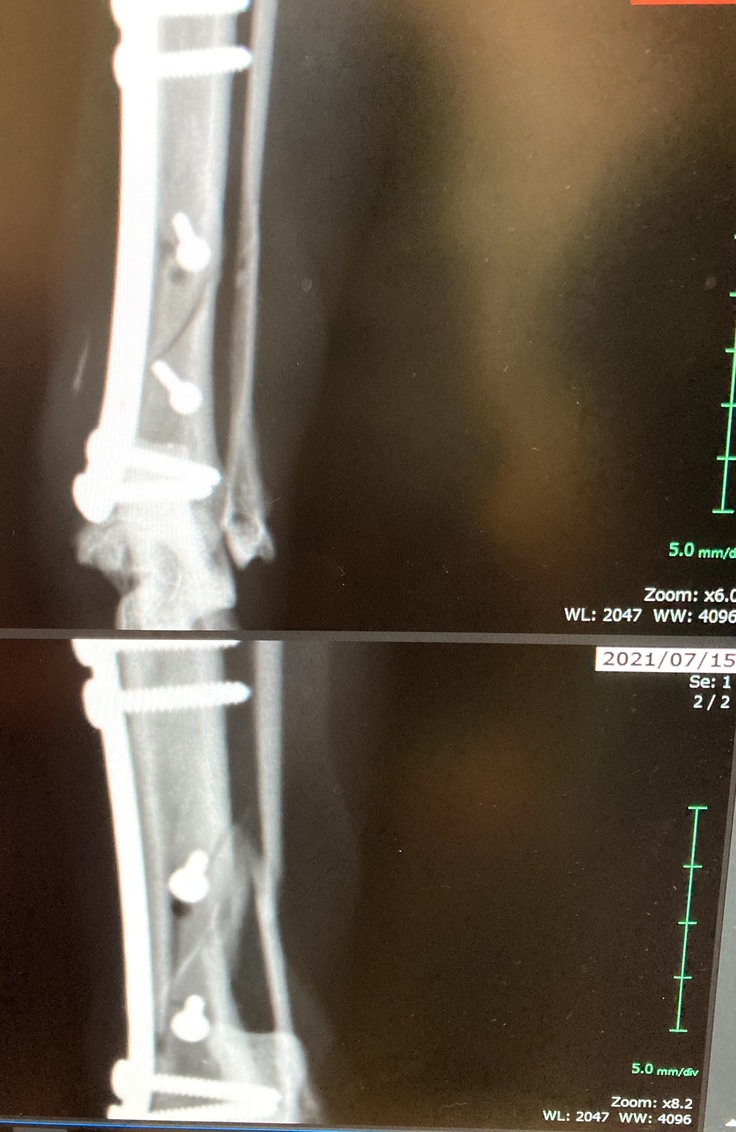

今回このくーちゃんが左後ろ足を開放性剝離骨折してしまいました。骨が3分割と小さな骨に分かれてしまっていてプレートを入れ小さい骨はピンで止めていただき手術は大成功しました。しかし創部に感染があった為術後も入院が長引きました。退院して2日後又発熱しぐったりし受診、感染からの熱か再入院。その退院の2日後にまた患部が凄く熱くぐったりし受診。今回は手術の部位が再度骨折してしまっていました。毎日ケージの中でほぼほぼ寝たきりであったのですが何故か再度骨折。かなり痛みもある様で可哀想に熱もでていました。私は死んでしまうのではと夜中に何度も見に行く日々が続きました。

悲しいことに手術してもらった所が再度骨折。

上が7月10日、下が15日 真ん中の小さい骨がずれてピンが横を向いてしまっています。

現在ケージで安静にしていますが創部の感染のため骨ができにくく今後も再手術、最悪の場合切断の可能性は否定できないとDrより説明を受けています。

9月17日現在、骨折の方は新しい骨が少しづつ出来てきていました。心配していましたが、良かったです。少しほっとしました。しかし骨形成は遅くまだこれから1か月半位安静必要だそうです。今まで寝てばかりでしたが、最近はお座りも出来るようになってきました。

9月17日上の写真です。空いていた穴が少しずつ塞がって来ているとの事です。